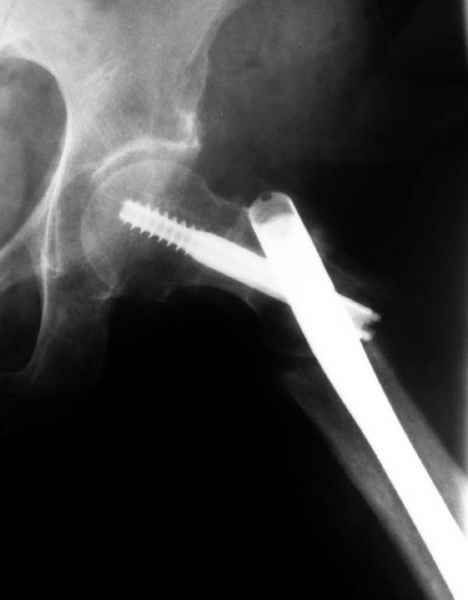

77 летняя больная направлена в нашу клинику на дальнейшее лечение. Из истории, травму получила в сентябре 2007 года и по поводу перелома шейки бедра больная была проперирована тремя каннюлированными шурупами с явным нарушением технологии установки шурупов. Внизу вместо одного шурупа имеется два, что привело к стрессу латерального кортекса. Через месяц по поводу ятрогенного подвертельного перелома сделана фиксация длинной Гамма 3. Установлен без проксимальной блокировки? (set screw). В данный момент имеется несостоятельность конструкции и ложный сустав. Передвигается с помошью костылей, конечность укорочена на 2 см. Какие будут рекомендации?Djoldas Kuldjanov, MDDepartment of Orthopedic SurgerySt. Louis University Medical Center

Видимо, проблем тут две: во-1-х, центральный отломок был оставлен в варусно-сгибательной установке, во-2-х, не динамизировали вовремя.

Нижние винты хотели сломаться, но, увы, один не сломался, и тогда сломался гвоздь. Хотя и при динамизации в таком положении отломков

могло не срастись.

Михаил, здравствуйте. Если присмотреться - на четвертом снимке есть перелом гвоздя по отверстию.